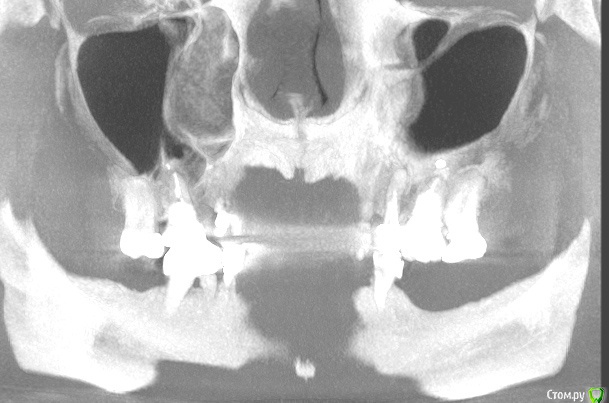

Clearr Опубликовано 8 июля, 2015 Поделиться Опубликовано 8 июля, 2015 Добрый день. Прошу вашего совета!! Объем имплантации в 10 зубов получается немаленький. На сегодняшний день предлагается 2 плана:1. первоначальное удаление ВСЕХ! (7,6,5 слева вверху, 6,5 справа вверху и 6 снизу) проблемных зубов, пролечивание и только потом операции по костной пластике и лифтингу. Объясняется тем, что наличие очагов воспаление в полости гарантирует плохое приживление костной ткани. Итого: либо единомоментная обширная операция на 2 челюстях , либо 2 года без зубов, но потом счастье. 2. 1. Удаление 3-х зубов наверху слева с одномоментным синуслифтингом и костной пластикой на нижней челюсти также слева. В данном случае рабочей останется правая сторона.2.Через 6 месяцев установка имплантатов -2 или 3 штуки верхняя челюсть слева, 2 штуки нижняя челюсть слева3.Через 3 месяца- протезирование на имплантатах с левой стороны на верх.и ниж. челюстях, левая сторона введена в строй4.Удаление 2-х зубов на верхней челюсти справа с одномоментным синуслифтингом и НТР в области 4-го ( там, где потеряна кость), а также удаление 6-ки внизу справа ( там воспаление)5. через 6 месяцев установка 3-х имплантатов на верхней челюсти справа и 2-х на нижней челюсти справа6.через 3 месяца протезирование на имплантатах с левой стороны верх и низ. Все равно получается очень много и дорого. Действительно ли надо удалять все эти зубы, даже если они не беспокоят? 7ка с кистой - обнозначное удаление или можно пролечить? Ссылка на КТ https://yadi.sk/d/PLaMcjgPhbGor Ссылка на комментарий

Clearr Опубликовано 9 июля, 2015 Автор Поделиться Опубликовано 9 июля, 2015 Спасибо за отзыв. еще один снимок в другой проекции. есть ли киста на 7 зубе? Ссылка на комментарий